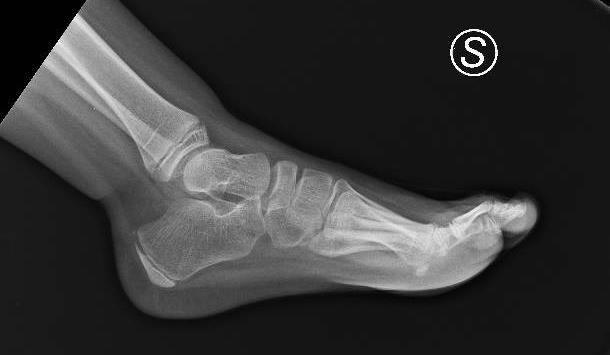

• Passive mobilization shows joint limitation at the tibiotarsal level

• Tibiotarsal dorsiflexion poorly reducible to 90 , with initial retractions

´Following orthopedic specialist visit, surgical correction of bilateral equinus foot was indicated

Fibrotomy-based Achilles tendon lengthening performed, achieving correction of equinus